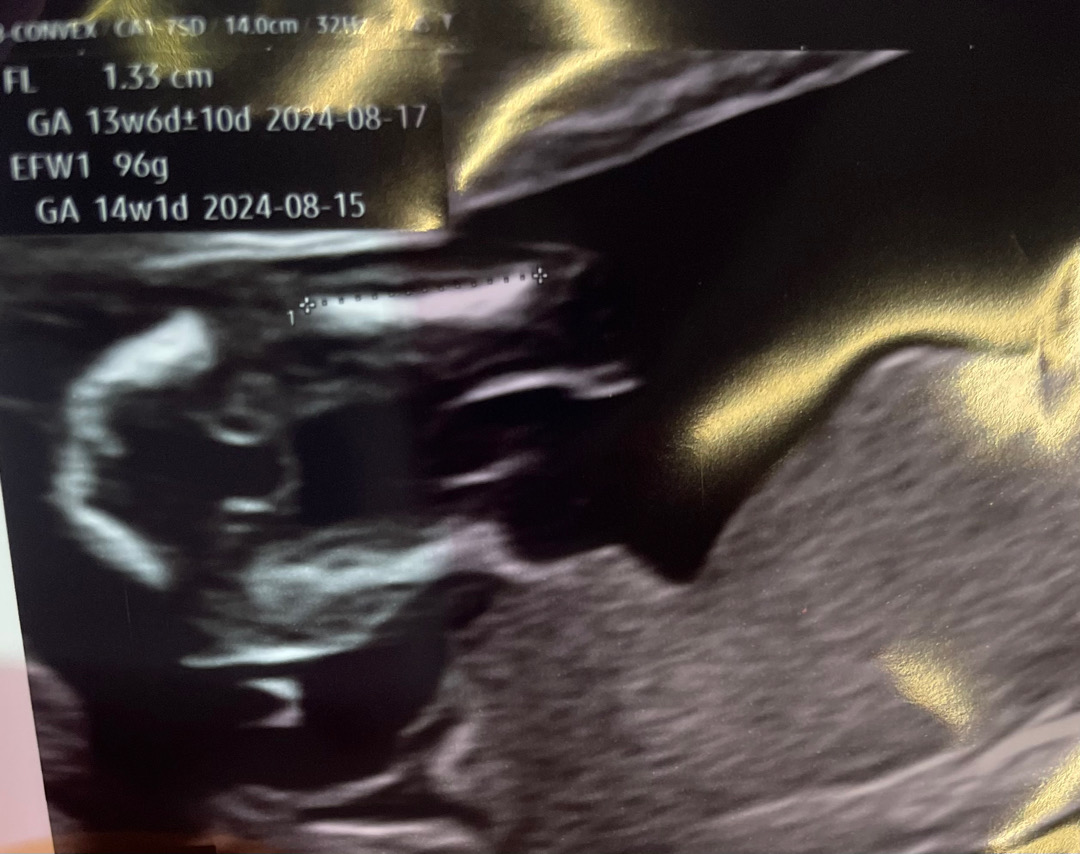

14주5일 성별 한번만 봐주세요!

다들 어때보이시나요???

저도 딸같아요! 14주 0일인데 로켓 확실히 보여주더라구요!

ㅋㅋㅋ 저희아가랑 비슷한데용 저도 알려주진 않았는데 이렇게 나왔어용 초음파